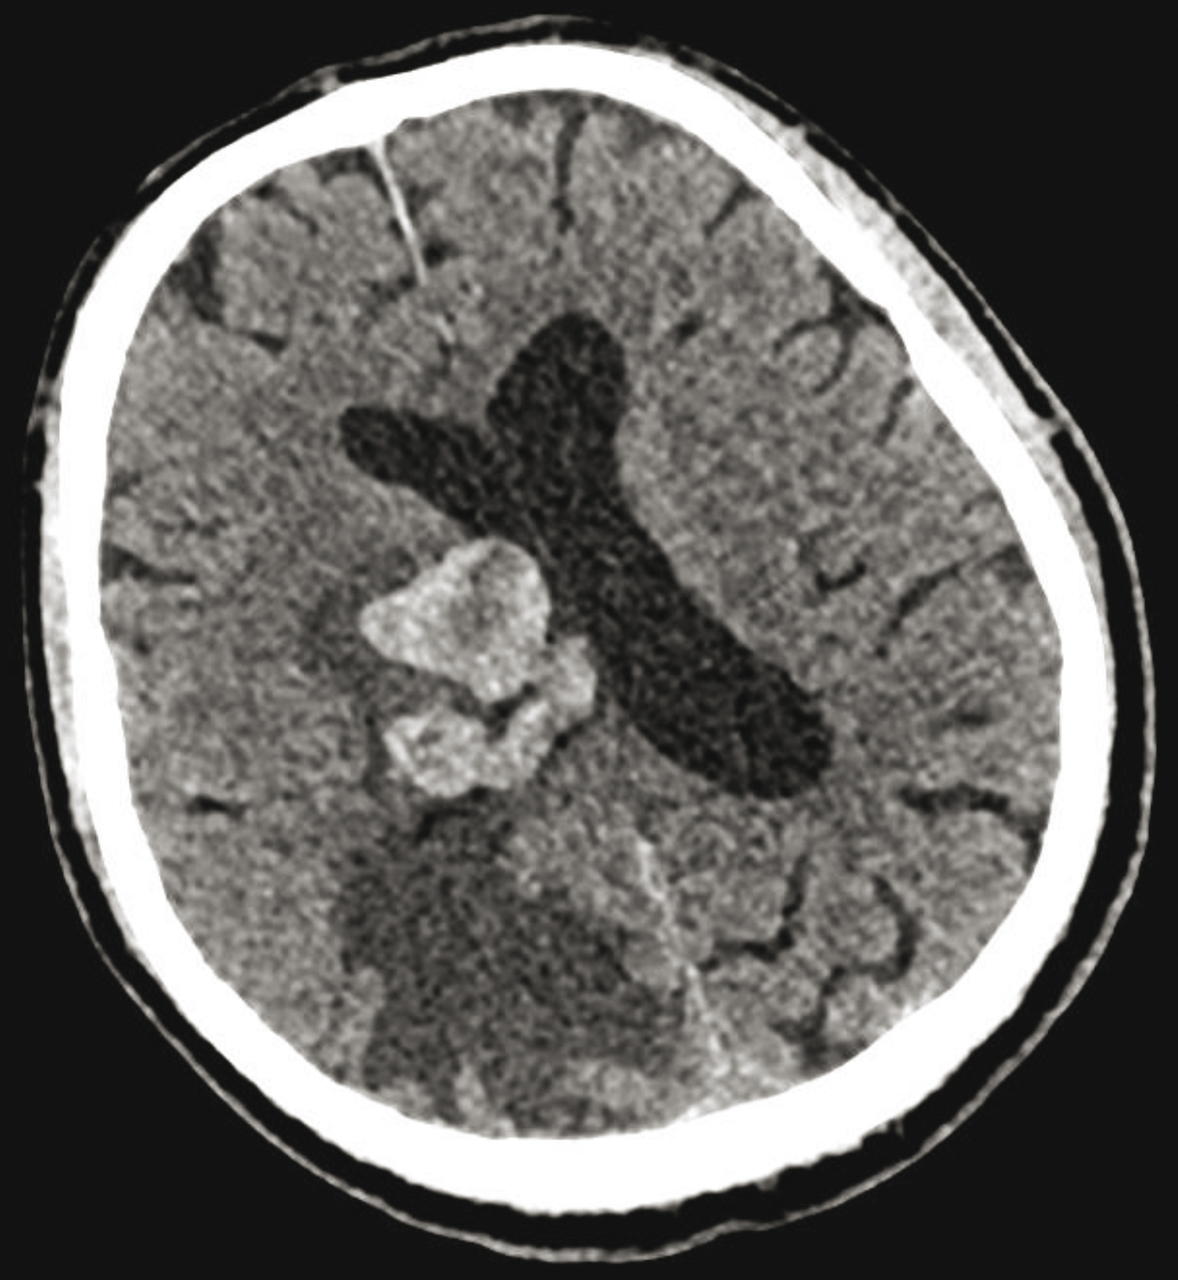

Quel est votre diagnostic ? Métastases cérébrales Il s'agit de métastases cérébrales.Pour en savoir plus :- Hoang-Xuan K, et al. Dossier. Métastases cérébrales : d'abord ne pas se décourager. Rev Prat 2014;64(5):667-88. Glioblastome Tuberculome Toxoplasmose cérébrale Lymphome OK Valider mes réponses